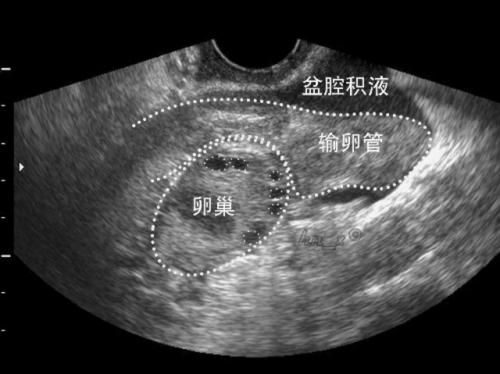

其实,这么丰富的联想有些杞人忧天了,体检发现有盆腔积液不一定就是盆腔炎症。盆腔积液本身并不是一种疾病,它只是B超影像学检查的一种表现。

具体到女性的盆腔积液,有些积液是生理性的,主要有排卵期的卵泡液,月经期的经血也可能逆流进入腹腔,这些盆腔积液,都是可以慢慢被吸收的。

也有一些病理性积液,包括阑尾炎、盆腔感染等引起的炎性渗出液。还有些是异位妊娠、黄体破裂、出血性的输卵管炎造成的出血。极少数积液更危险,是卵巢癌、子宫、输卵管、胃肠道肿瘤引起的。出现了这种积液,对怀孕有严重的影响。